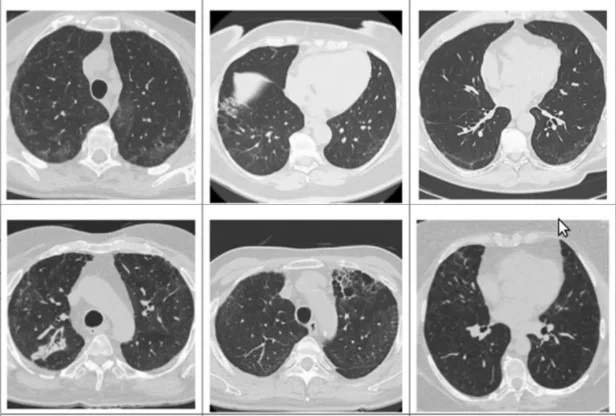

Phim X-quang của bệnh nhân N.T.T. (56 tuổi) mắc di chứng hậu Covid-19, được chẩn đoán xơ phổi và suy hô hấp mức độ nặng, đến khám tại Bệnh viện Đại học Y Dược TP.HCM. Ảnh: Duy Hiệu.